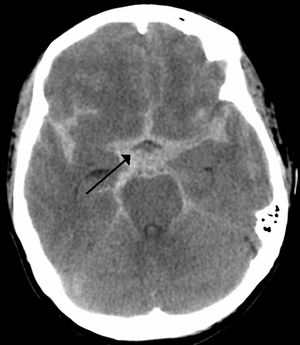

As first postulated by Harvey Cushing, raised intracranial pressure is the primary cause of the Cushing reflex.[3] Furthermore, continued moderate increases in cranial pressure allows for the Cushing reflex to occur. In contrast, rapid and dramatic pressure rises do not allow for the mechanism of the reflex to sufficiently take place.[12] Elevated intracranial pressure can result from numerous pathways of brain impairment, including: subarachnoid hemorrhages, ischemia, trauma, including concussions, hypoxia, tumors, and stroke. In one study, it was confirmed that raised ICP due to subarachnoid hemorrhaging causes mechanical distortion of the brainstem, specifically the medulla. Due to the mechanism of the Cushing reflex, brainstem distortion is then swiftly followed by sympathetic nervous system over activity.[13] In addition, during typical neurosurgical procedures on patients, especially those involving neuroendoscopic techniques, frequent washing of the ventricles have been known to cause high intracranial pressure.[7] The Cushing reflex can also result from low CPP, specifically below 15 mmHg.[14] CPP normally falls between 70-90 mmHg in an adult human, and 60-90 mmHg in children.